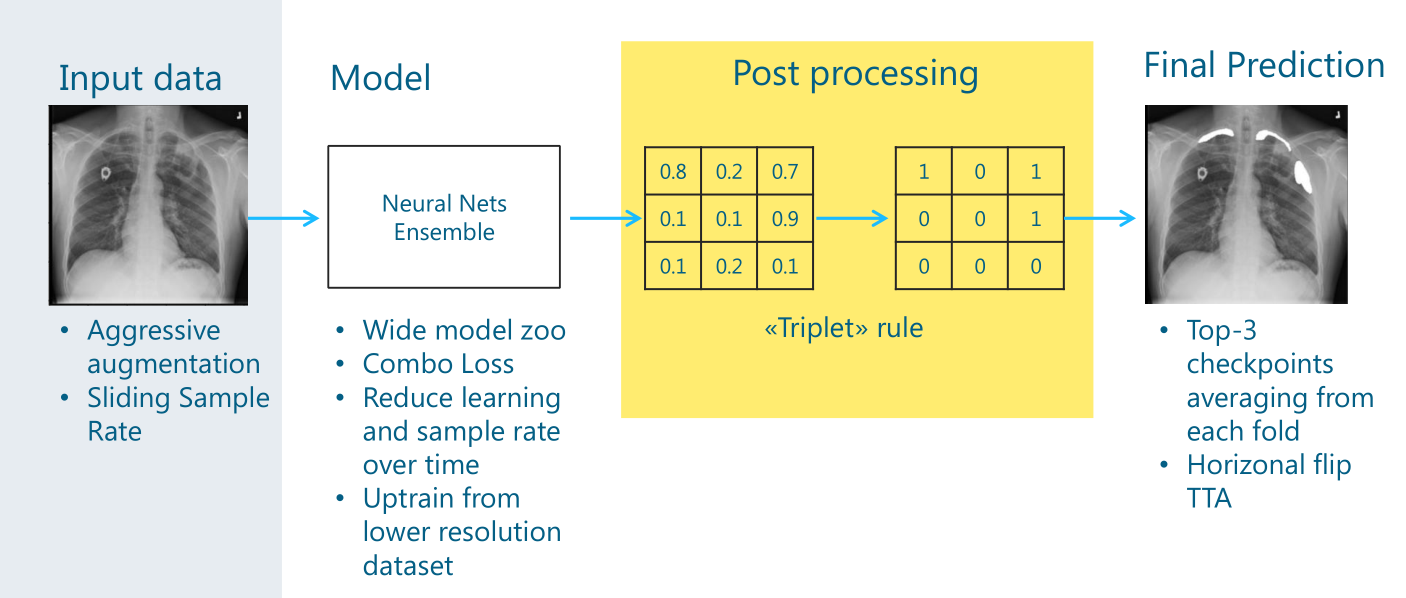

3.1 Data Augmentation

这里模型的输入是1024X1024X3的胸片和1024X1024X1的mask。作者直接使用了图像增强库 albumentations 对数据进行增强,作者使用了一个较为复杂的方案:以固定顺序对图像进行不同的变换,并且给予每种方法一定的概率,使增强方法的运用随机化。具体如下:

- HorizontalFlip:0.5

- OneOf:0.3

- RandomContrast:0.5

- RandomGamma:0.5

- RandomBrightness:0.5

- OneOf:0.3

- ElasticTransform:0.5

- GridDistortion:0.5

- OpticalDistortion:0.5

- ShiftScaleRotate:0.5

上面小数表示此增强方法运用的概率,OneOf表示在其子方法中选择一个。

需要注意的是,这里有2个OneOf,第一个OneOf下面的增强方法主要对图像的亮度、对比度等进行调整,而第二个OneOf下面的增强方法主要对图像的形状进行调整。可以看几个例子。

因为训练模型分成四个阶段,每个阶段使用的数据是一样的,使用一定概率给图像做增强,实际上保证了每个阶段实际参加训练的数据都不完全一样。